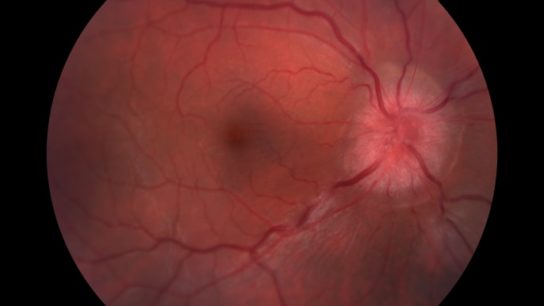

Those treated with phenytoin saw a 30% reduction in retinal nerve fiber loss.